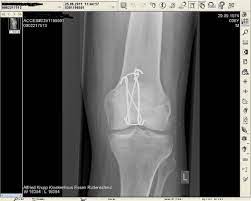

Löcher im knochen nach metallentfernung. Die ist hart und sehr spitz und lässt sich nicht bewegen. Obwohl ein Schraubenloch noch lange im Röntgenbild nachweisbar ist kommt es zu einer fortschreitenden Geflechtknochenbildung die die Stresskonzentration im Schraubenloch zunehmend herabsetzt. Bei Knie-OPs wird die Metallentfernung in der Regel cirka nach einem Jahr durchgeführt.

Immerhin wird das Bein bin zum Knochen geöffnet Gewebe und Muskeln durchtrennt und es verbleiben Löcher in den Knochen. Die Schraube im Schenkelhals ließ sich noch lösen die zwei Verriegelungsschrauben jedoch nicht - die Schraubenköpfe brachen ab die Gewinde wurden überbohrt und brachen wieder ab. Da die Drähte bei auch nur leichter Lockerung eine Gefahr für Strecksehen darstellen gibt es sehr gute Gründe die Kirschnerdrähte zu entfernen.

Obwohl sehr selten kann es im Rahmen der Metallentfernung ua. Nein dies ist ein völlig normaler Befund.

Gelegentlich ist es nicht möglich das Material vollständig zu entfernen so dass es auch vorkommen kann dass Reste des Metalls im Körper belassen werden müssen. Ich habe neulich das Gleiche bei einem Schrank erlebt. Die Stabilität sollte nach der Entfernung kein Problem sein weil die Schrauben und Nägel immer versetzt angeordet sind also die Löcher nie über- untereinander lägen. Die ist hart und sehr spitz und lässt sich nicht bewegen. Sollten Metallteile weggebrochen sein werden die dann auch im Knochen belassen die tun nix. Hier ist die Radiusfraktur nicht mit einer Platte sondern mit Kirschnerdrähten erfolgt. Obwohl ein Schraubenloch noch lange im Röntgenbild nachweisbar ist kommt es zu einer fortschreitenden Geflechtknochenbildung die die Stresskonzentration im Schraubenloch zunehmend herabsetzt. Hierbei wird in manchen Fällen lediglich die einzelne Stellschraube entfernt wobei die komplette Metallentfernung ungefähr nach einem Jahr beginnt. Auch nach einem Jahr kann man im Röntgenbild nach einer Schraubenentfernung die Schraubenkanäle gut erkennen.